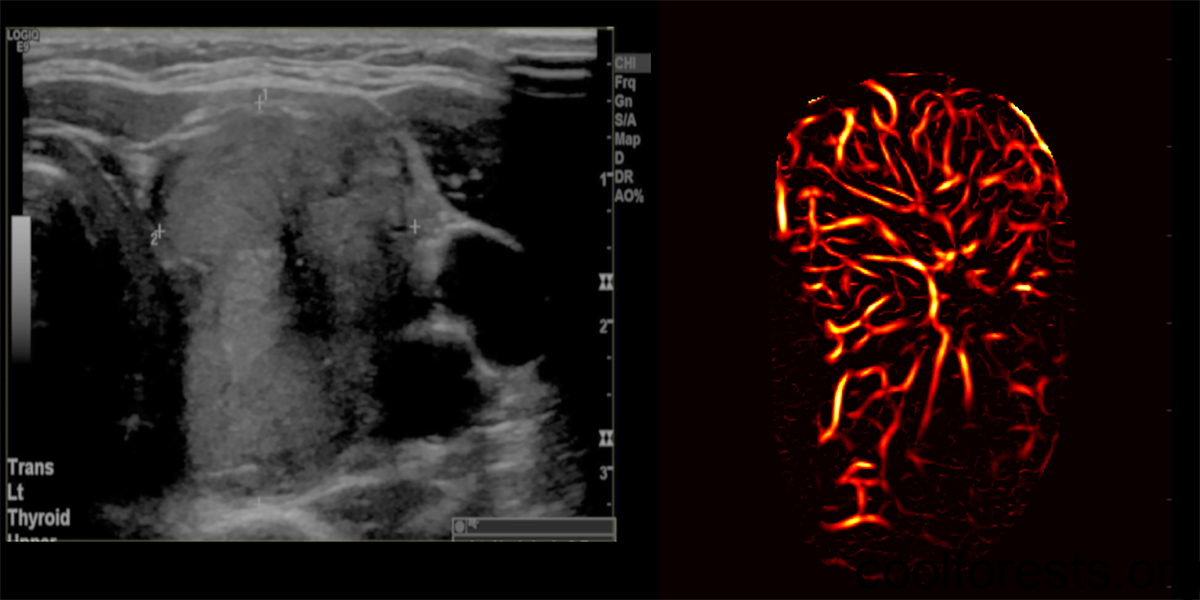

The method — deemed high-definition microvasculature imaging, or HDMI — noninvasively captures images of the tiny vessels within tumors and, based on the vessel features, automatically classifies the masses. Researchers at the Mayo Clinic College of Medicine and Science, who developed the technique, tested it on 92 patients with thyroid tumors, finding that the method could distinguish if the growths were cancerous with 89% accuracy. In a study published in the journal Cancers, the authors suggest that HDMI could potentially resolve a long-standing diagnostic challenge of assessing thyroid tumors in the clinic.

The researchers took pictures of the tumors with HDMI and measured a dozen features related to the size and shape of the microvasculature in the images, including their density and number of branching points.